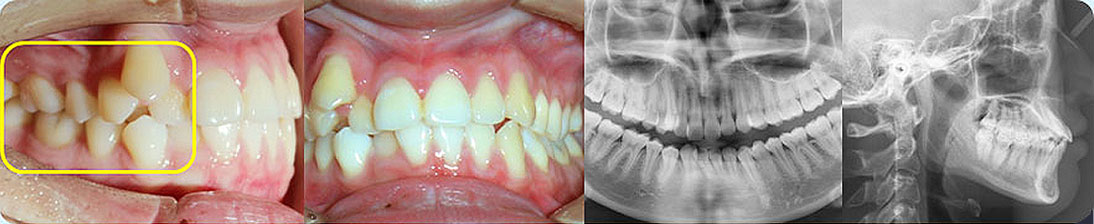

矯治采用兩種不同的厚度的膜片(牙套),發揮兩種不同膜片的各自優勢,在有效的作用時間內,矯治效率、矯治目標達成和舒適度方面較普通隱形矯正方式有明顯提升。

厚薄兩種矯治器,每周替換有利于牙齒位置的準確控制